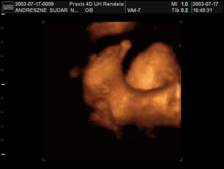

Combocska